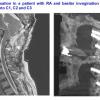

A typical indication is the so-called basilar invagination, which is when the cervical spine, especially the dens axis is partly shifted into the head by the spinal canal and therefore damages the brain stem. This can occur in rheumatoid arthritis.

Rheumatic disorders can cause a wide range destruction of the head and neck area. The most common ones concern the dens (i.e. the second cervical vertebrae). It may change greatly inflammatory and may therefore constrict the spinal canal. Previously thisinflamed pannus was removed through the mouth (transoral). Today we know that a stabilization operation is sufficient to ensure the involution. Often a C1-C2 stabilization is enough. Sometimes, however, the occiput has to be involved.